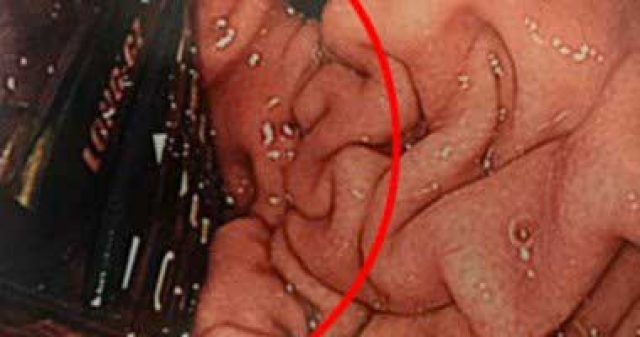

ونتيجة لذلك، قرر الأطباء إدخال المنظار مع ضوء وكاميرا فيديو في النهاية، حتى يتمكنوا من تحديد موقع الهاتف وسحبه من معدة المريض عن طريق المريء. ولكن عندما فشل هذا اضطروا إلى إجراء عملية فتح البطن، حيث فتحوا شقا كبيرا في البطن، وتم استخراج الجهاز بنجاح، وعندما تم قياس الجهاز ذلك، تبين أن أبعاده 6.8 × 2.3 × 1.1 سم.